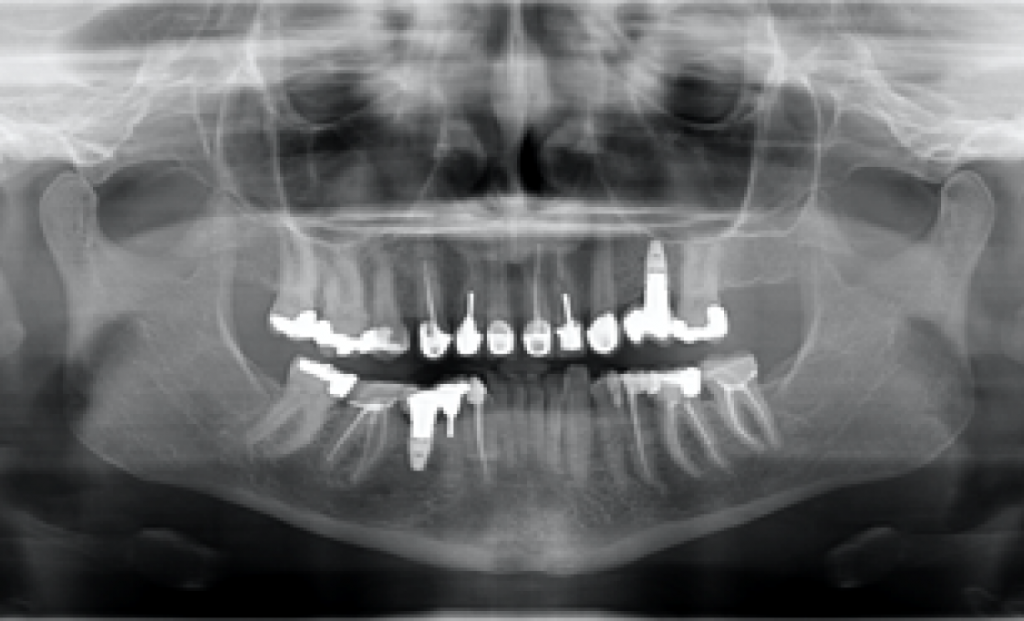

Выбор одинарного абатмента был упрощен благодаря семейству ti-base, принятому большинством производителей имплантатов. Эти абатменты имеют ретенционную часть, к которой экстраорально прикрепляются изготовленные в лаборатории протезы. Абатменты бывают разного диаметра и высоты десневой манжеты. Выбор правильной высоты и диаметра должен осуществляться клинически. Проблема стандартизации этой очень простой процедуры иллюстрируется рентгеновским изображением на рис. 1.

Этот пациент обратился ко мне с жалобами на сильную боль, покраснение и отек вокруг только что установленной коронки на имплантате. В анамнезе было следующее: был снят аналоговый оттиск с уровня имплантата и отправлен в лабораторию для изготовления коронки. У лаборанта не было указаний относительно расположения шейки имплантата по отношению к мягким тканям и кости.

Была выбрана самая короткая высота десневой манжеты (GH), так как она является наиболее безопасной с эстетической точки зрения, поскольку металлическая кромка не будет видна над десной. При доставке коронки на имплантат стоматолог столкнулся с трудностями при «посадке» коронки на абатмент.

Коронка была установлена со значительным сопротивлением для достижения необходимого значения торка. Ущемление твердых и мягких тканей из-за очень острого профиля выступа вызывает давление на кость, что приводит к некрозу и, в конечном итоге, к потере маргинальной кости в этой области. Чтобы избежать подобных осложнений, необходимо выбирать правильный абатмент.

На основе ОПТГ, сделанного после установки или имплантата (рис. 2), стоматолог может выбрать подходящую высоту десневой манжеты для абатмента и направить техника, предоставив рентгеновский снимок и/или спецификацию формирователя десны. Большинство систем имплантатов имеют синхронизированные формы и контуры хирургических абатментов и компонентов протеза.